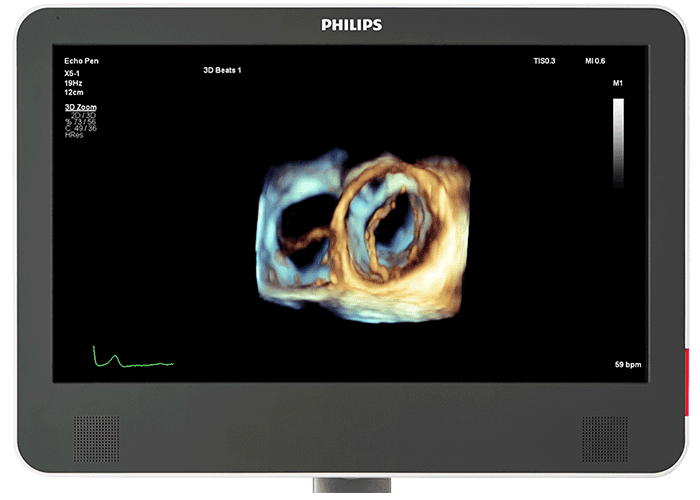

実績のある xMATRIX アレイトランスジューサと PureWave クリスタルテクノロジーにより、トランスジューサを持ち替えることなく 2D 画像および Live 3D 画像を提供します。X5-1c は、画質を損なわない 3D およびカラー 3D のワンビート画像を含め、すべてのイメージングモードに対応しています。X5-1c で撮影した 3D ボリューム画像は、優れた実績を誇る 3D Anatomical Intelligence Ultrasound(AIUS)ツールである Dynamic HeartModel も使用可能です。その場合、画像最適化において一貫性を確保する、acquisition モードと設定を使用します。

定量化に確信をもたらす HeartModel は、ルーチンワークフローの一部として、確実で再現性のある駆出率(EF)をわずか数秒で提供する 3D ツールです。Dynamic HeartModel は、左室(LV)および左心房(LA)の Volume カーブを表示します。また、LV Mass および LV Mass Index などの計測が可能です。Dynamic HeartModel では、複数の心拍解析が可能になり、不整脈と思われる患者の定量化も行うことができます。EPIQ CVx Transcend を見た臨床医の 78%¹が、画像品質の向上、視覚化ツールの進歩(TrueVue や有機 EL モニタ画面など)、Dynamic HeartModel(進化した HeartModel)²により、診断に対する確信を高めることができると回答しました。